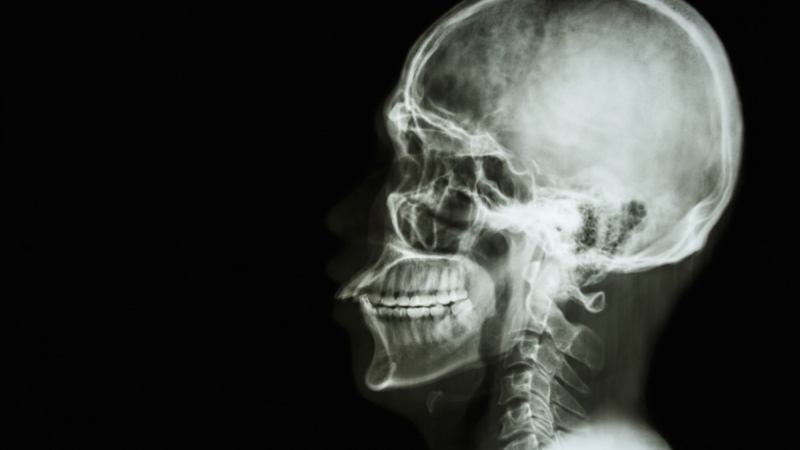

Kidney transplants have become routine, and heart transplants are increasing in prevalence with huge success rates. But, there’s a whole new school of thought coming our way, and some of it sounds incredible, if not impossible. Valery Spiridonov, a 30 year-old Russian man who suffers from Werdnig-Hoffman Disease, has been in touch with Italian neurosurgeon Dr. Sergio Canavero, who hopes to perform the first head transplant by 2017. Spiridonov believes that this transplant, albeit a risky one, is his only hope to escape the rare neuromuscular disease. According to various news reports, it looks like the surgical operation will require a team of 100 and cost an estimated US$15 million. The risks appear endless, and many other medical workers believe that it will also take a while before Dr. Canavero, who is also Director of the Turin Advanced Neuromodulation Group, can perform the surgery he claims has a 90% chance of success.